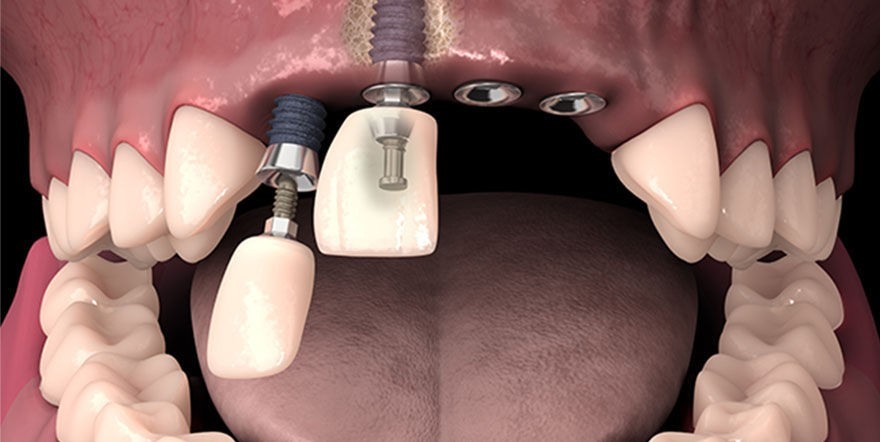

Сапдвач, вы тут живые? Есть кто по специалистам кто или по пострадавшим совсем?

Интересует тема имплантации, что ставили, как долго восстанавливались, что у вас с функцией ПОЖРАТ, что вам предлагали ставить, на что согласились.

Сделали мне цистэктомию с удалением зуба переднего (резца), консервативное лечение не помогло, попутно разъебали всю кость-десну и теперь огромный провал-долина на месте где зуб был. По КТ уже было видно огромную площадь кисты и сразу сказали что костную пластику надо делать, хотели сразу после удаления но хирург разрезав сказала что киста рыхлая и хуевая и не будет делать пластику т.к. высок риск отторжения материала.

Пока что зашила меня и отправила отдыхать, через неделю осмотр, примерно через месяц сказала можно подумать будет над пластикой.

Алсо подскажите мне, нужно ли мне с имплантологом сразу до костной пластики знакомится-работать показаться или пластикой задача челюстно-лицевого хирурга заниматься, а к импантологу уже после месяца через 6 после пластики?

Аноним 05/09/25 Птн 23:46:20 1639107 100